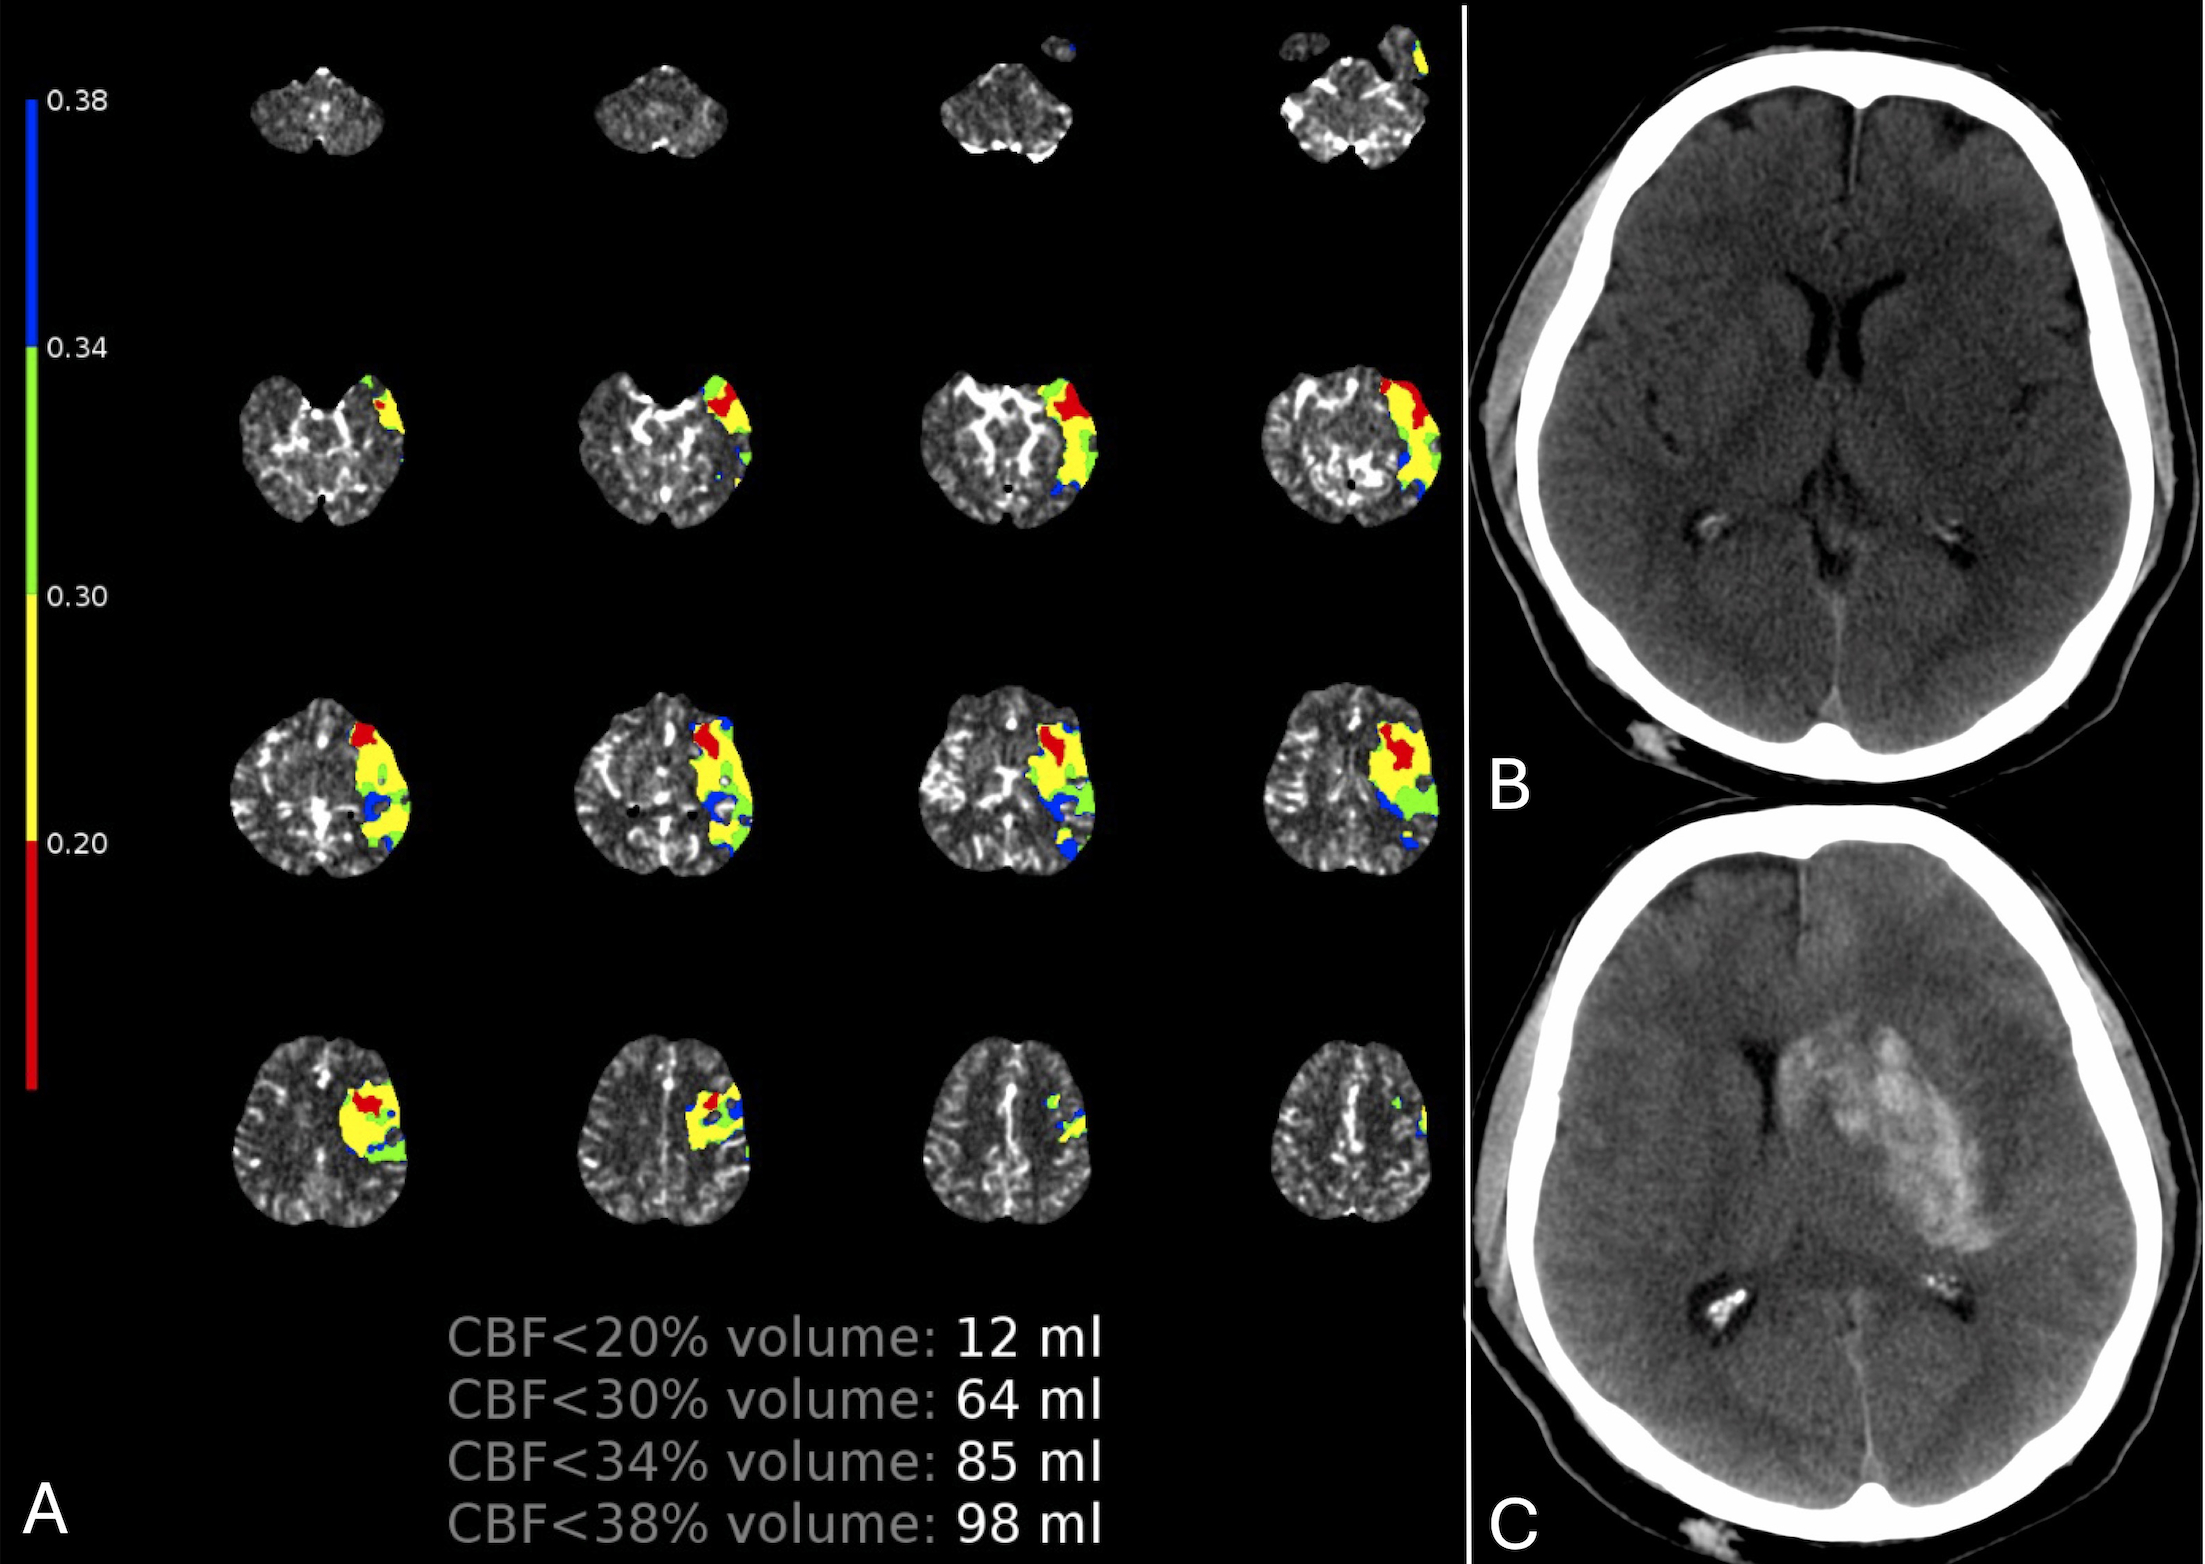

Methods: Data are from the ESCAPE-NA1 trial, which evaluated the effect of nerinetide in large vessel occlusion patients treated with thrombectomy. For this study, we included patients with some degree of recanalization (expanded Thrombolysis in Cerebral Infarct [eTICI] >0) and available baseline CT perfusion. Severe hypoperfusion was defined as at least 1mL volume of relative cerebral blood flow (rCBF)<20%. The primary and secondary outcomes were the presence of PH and of any HT, respectively, assessed on 24-hour imaging, according to Heidelberg criteria. The effect of time and severe hypoperfusion on outcomes was assessed with univariable and multivariable logistic regression analyses, including interaction terms to assess treatment effect modification.

Results: Out of 1105 patients from ESCAPE-NA1, 396 (35.8%) were included. The median age was 70 years (IQR=59.8-79.2), 202 (51%) were females, and 50 (12.6%) experienced PH. Onset-to-imaging time (adjusted OR 1.04 [95%CI=1.01-1.06] per 15-minute increase) and the presence of severe hypoperfusion (adjusted OR 2.63 [95%CI=1.21-5.72]) were the only variables associated with PH in multivariable analysis. No significant interaction effect of time and severe hypoperfusion on PH was found. The presence of severe hypoperfusion has a negative predictive value of 98% and a positive predictive value of 39.4% for predicting PH in patients presenting within three hours and after six hours from symptom onset, respectively.

Conclusion: Both severe hypoperfusion and time affect the risk of hemorrhagic transformation in ischemic cerebral tissue. Analyzing these variables may help identify patients with a leaky, severely compromised blood-brain barrier in the ischemic core—a “leaky core.”